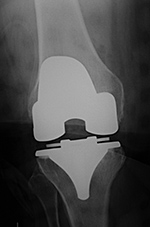

| 65 year-old woman with bilateral cruciate-retaining total knee arthroplasties (TKAs) placed in early 2009. In November 2015 routine follow-up showed bilateral aseptic loosening in both tibial components with wide periprosthetic lucencies (arrows) and varus deformity on the left. From left to right, respectively, AP radiograph of the right knee in the immediate postoperative period, AP radiograph of the right knee 6.5 years later, and standing frontal view of the knees 6.5 years after surgery. Images courtesy Laura H Lee, MD. |